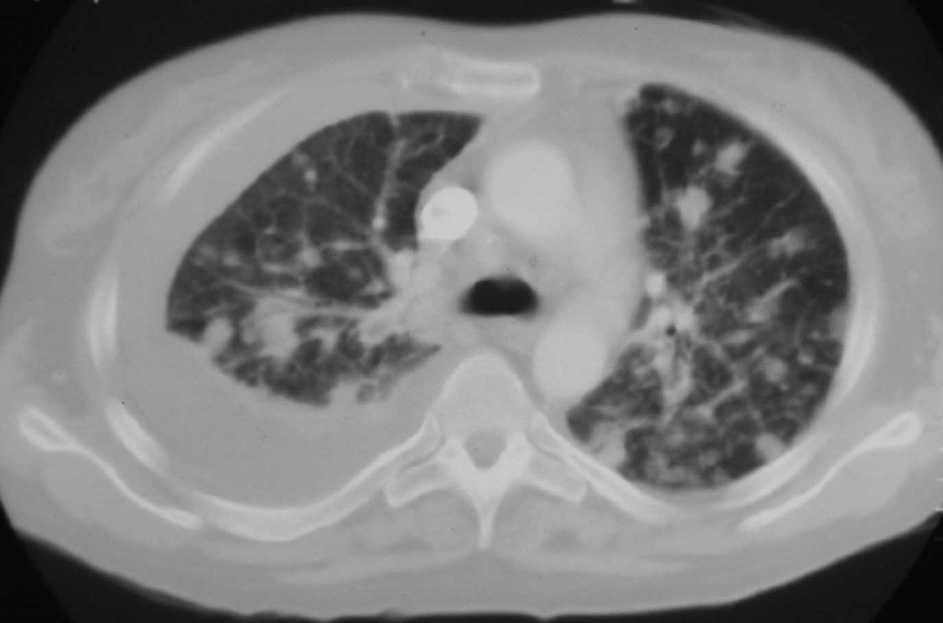

Fig. 3. Tomografía computarizada a la altura de la carina.